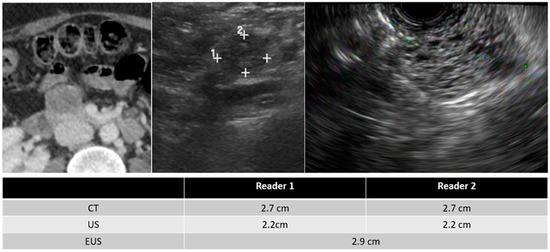

| Mean size of detected PCLs (cm) | ||

| TAUS | 2.40 ± 2.65 | 2.41 ± 2.56 |

| CT | 2.45 ± 2.43 | 2.48 ± 2.53 |

| EUS * | 2.73 ± 2.10 | |

| Intra-reader variability in measured size | Reader 1 vs. Reader 2 | |

| TAUS | −0.01 ± 0.39 | |

| TAUS vs. CT | TAUS vs. EUS | CT vs. EUS | |

| All PCLs (cm) | |||

| Reader 1 | −0.16 ± 0.53 * | 0.13 ± 1.14 | 0.15 ± 0.65 * |

| Reader 2 | −0.19 ± 0.55 * | 0.18 ± 0.81 | 0.22 ± 0.90 |